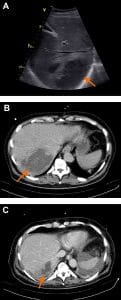

The most common pleural effusion location was left-sided in ten patients (58.8%) and bilateral in three (17.6%). Pleural fluid was homogenously echogenic in six (35.3%) patients and complex septated in five patients (29.4%). The mean (SD) size of pleural effusion was 3.7±2.46 cm (740±246 ml). These and other pleuropulmonary characteristics of the patients presenting with pleural effusion are shown in Table 3. Pleural effusion was only analyzed in two patients.

Pleural effusion has been associated with increased mortality in different pathologies including malignancies, infectious diseases, cardiac diseases, and liver diseases. It is considered a marker of disease severity and advanced organ dysfunction [2,17]. In this study, we found that ICU patients with septic shock and associated pleural effusion had significantly higher mNUTRIC scores and spent more days under mechanical ventilation than those without pleural effusion. Although there was no difference in mortality between the pleural effusion and non-pleural effusion groups, a tendency towards increased mortality in patients with pleural effusion (76.5% vs 60.7%) was noted. This finding contrasts with some studies that have reported an increased mortality in critical care patients with pleural effusion, although they did not analyze a specific group of patients with septic shock [1,2,17]. It should be highlighted that most of the studies reporting differences in mortality used chest radiography to identify pleural effusion, in contrast with the more sensitive chest POCUS, as we did [1,3,17,18]. This enabled us to identify small-to-moderate sized pleural effusion that could have gone unnoticed on chest radiographs, thus potentially affecting mortality outcomes. Chest POCUS has been reported to allow the identification of pleural fluid volumes as small as 5-20 mL, with a sensitivity of 100% when the volume is greater than 100 mL [19–21]. Therefore, it is more precise than chest radiography and has a similar level of accuracy to chest CT, which is the gold standard for the diagnosis of pleural effusion [19,20,22].

Moreover, in the sub analysis of patients with pleural effusion, a higher mortality was identified in those with a larger effusion size. This is consistent with studies on other diseases causing pleural effusion that used CT instead of chest POCUS[1]. However, the use of CT implies transportation of the patient to the radiology department, which may be impractical for ICU patients.